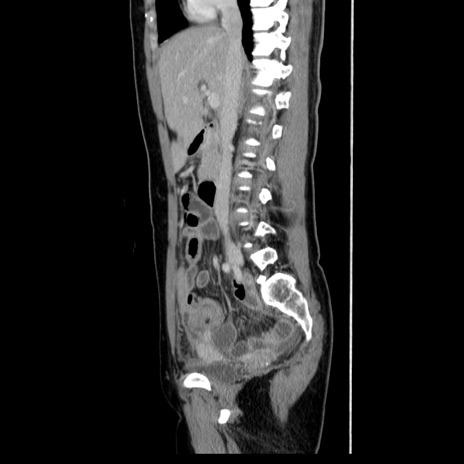

症例39(矢状断像)

CT